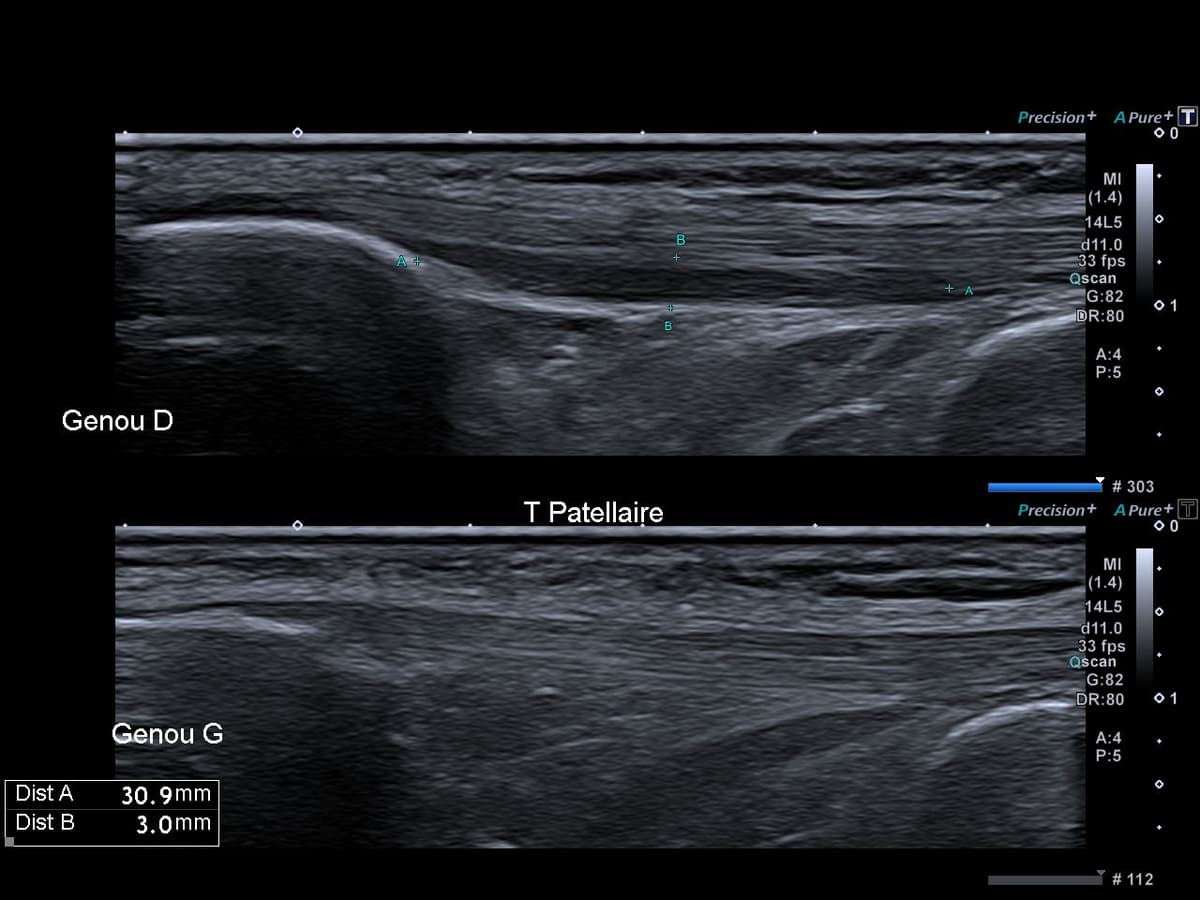

Gonalgie antérieure persistante à type de crise intermittente non prévisible ainsi que lors du passage en position accroupie.

US